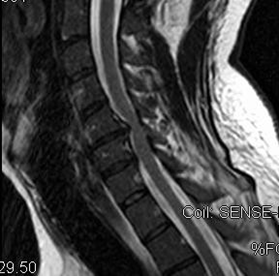

Laboratory findings were significant for macrocytic anemia (with hemoglobin of 9, MCV of 109), indirect hyperbilirubinemia 5.1, high LDH (1630), high retic count (3.7 %) and low level of vitamin B12 (159). Antibodies profile showed positive anti intrinsic factor antibody, high thyroid peroxidase antibody (270) and high thyroglobulin antibody.2 Cervical Spine MRI showed heterogeneous T2 hyperintensity with scattered enhancement in the bilateral posterior dorsal columns of the cervical cord with an inverted "V" appearance extending from C2-T1 as shown in Figure 1 & 2. Thoracic cord MRI demonstrates mild posterior column hyperintensity without enhancement.

Figure 1 Cervical MRI w/wo contrast, showing T2 hyperintensity with scattered enhancement in the bilateral posterior dorsal columns of the cervical cord.

Figure 2 T2 Sagittal MRI demonstrating hyperintense signal changes.